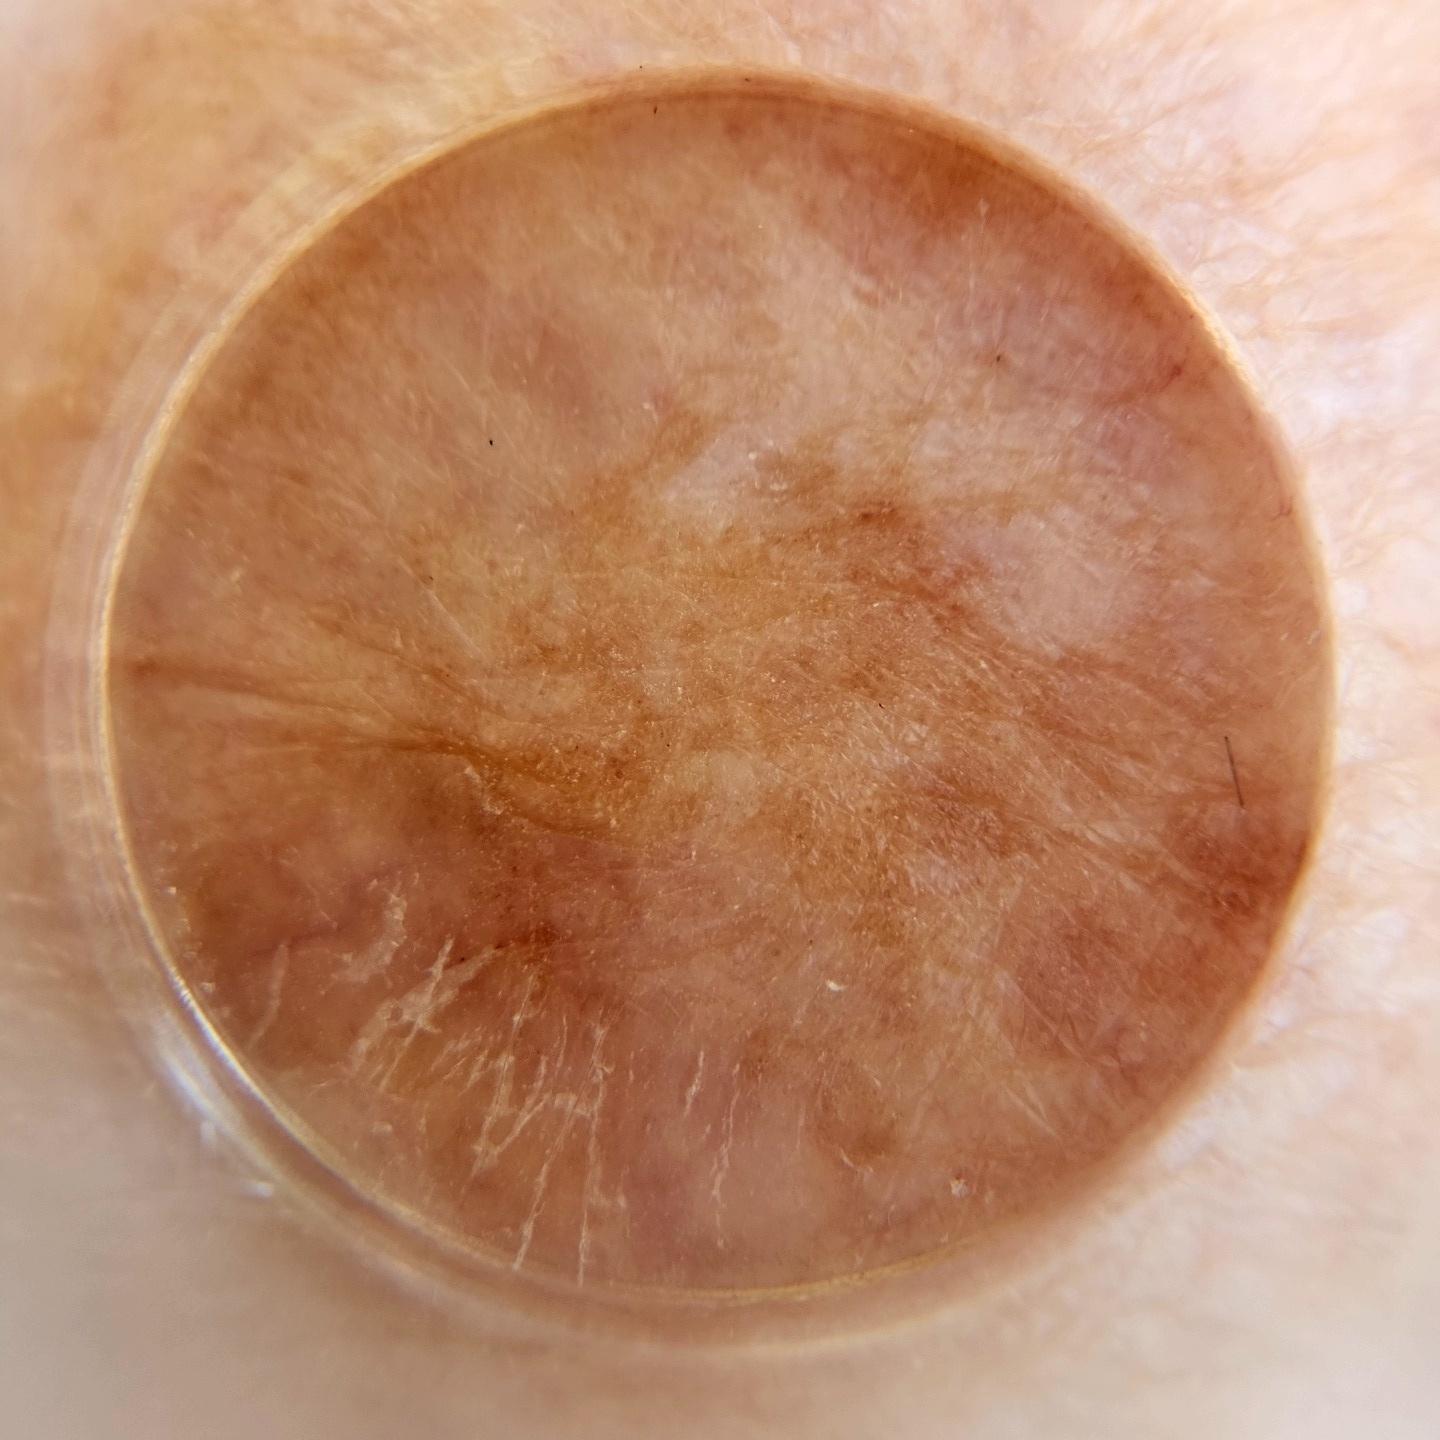

ISIC_4949599

Clinical

Field Value

diagnosis_1 Benign

image_type dermoscopic